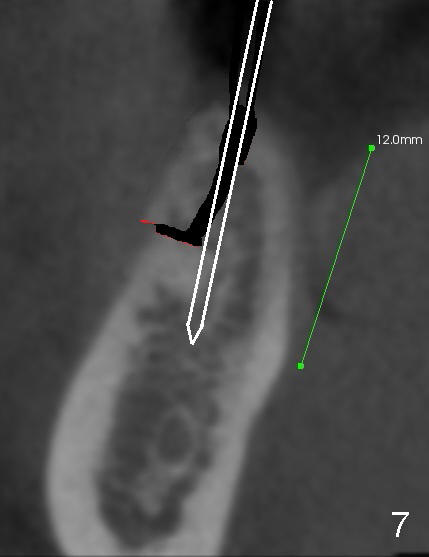

The ridge of the lower right molar is narrow buccolingually (Fig.1). After incision, ridge split is finished with a surgical fissure bur (Fig.2,3).

The patient is scheduled to return for implant placement 3 weeks later. The red lines in Fig.4 (CT coronal section) represent bony cuts in the ridge. A transverse incision is made over the top of the ridge with minimal exposure of the ridge. A curved osteotome is inserted into the upper bony cut (Fig.5). As the chisel is tapped in, the buccal segment moves buccally (Fig.6 pink arrow). When the chisel is withdrawn, a pilot drill is used to initiate osteotomy (Fig.7). As drills increase in diameter, the buccal segment continues moving buccally (Fig.8). Finally a bone-level implant (4.1 or 4.5x12 mm, Fig.9) or sub-crestal implant (4 or 4.5x8) is placed. Will the ridge split work?